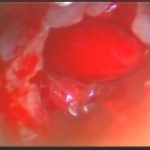

術中写真

摘出 前

摘出 中

摘出 後